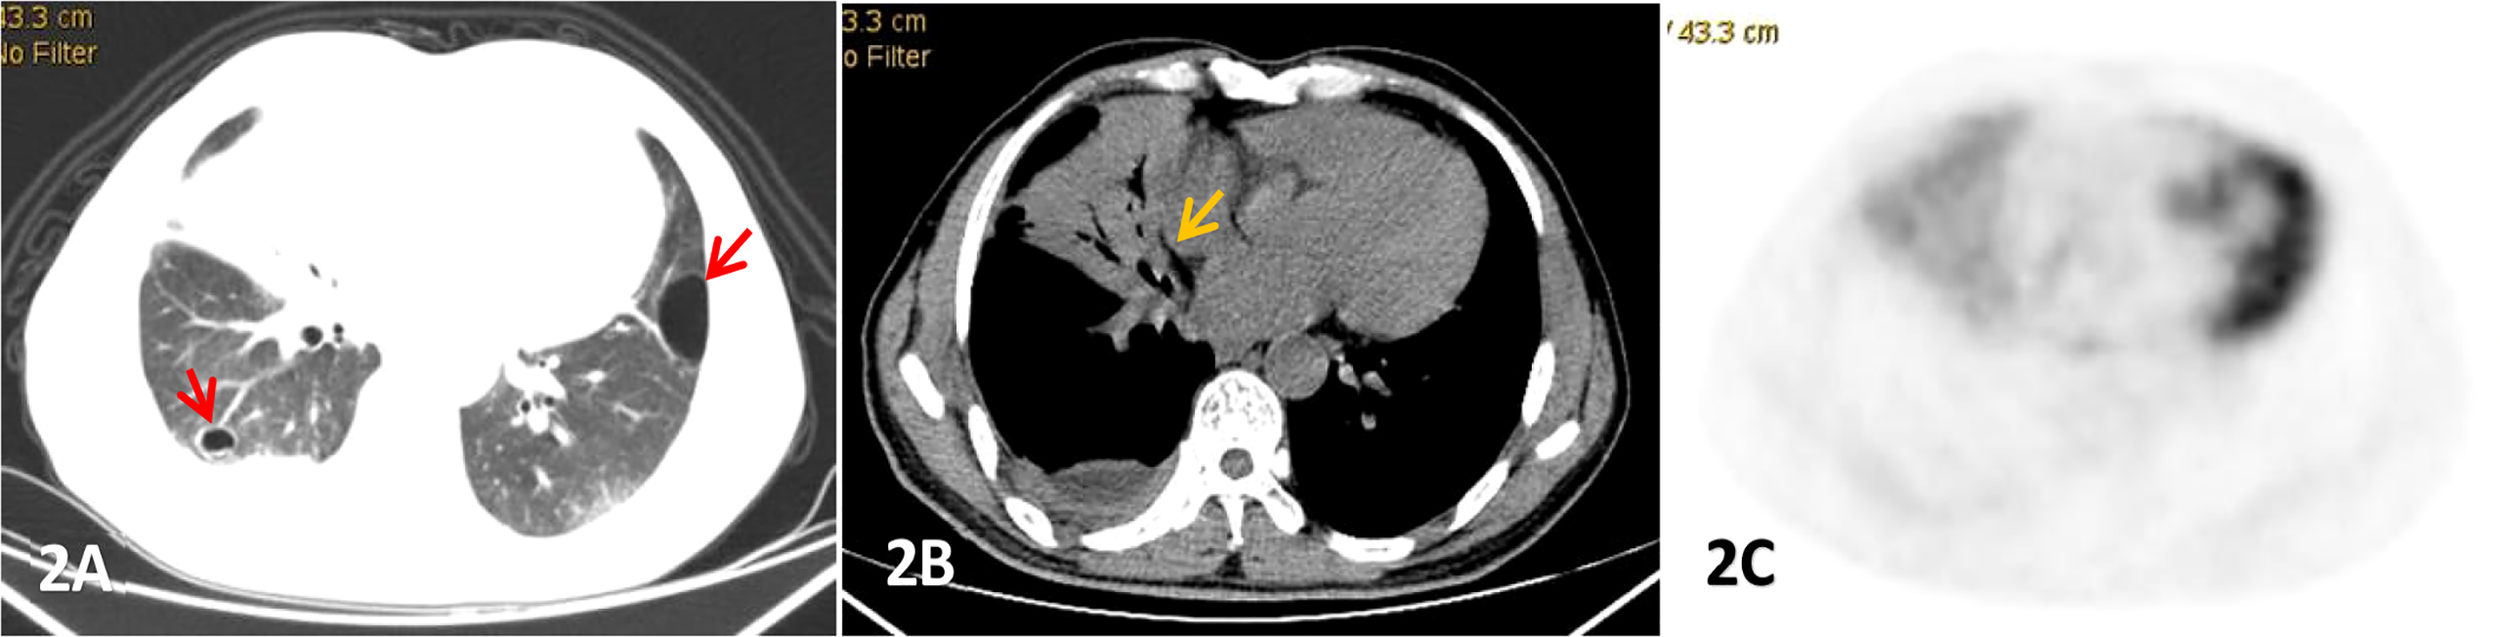

Figure 2

Male, 53 years old, cough and expectoration accompanied by right lower chest pain for more than 2 months, (A-C) were lung, mediastinum CT transection scan and PET transection image respectively,. Large consolidation shadow was showed in the middle lobe of the right lung with air bronchial signs(yellow arrow),which FDG uptake increased with an SUVmax of 3.83, right pleural thickening and pleural effusion, and cystic lesions(red arrow) were also observed in both.